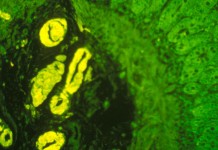

Амилоидоз – это заболевание, при котором в различных органах и тканях происходит отложение аномального белка, называемого амилоидом. Синтез амилоида происходит в клетках костного мозга....